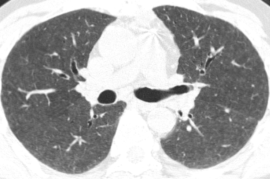

这是另外一个例子,双肺有斑片状的磨玻璃影,同时看到了有少量囊腔,还看到了正常密度的肺脏,双下肺靠近胸膜的地方有少量实变。

从这张图片上,我们看到两种密度,高密度的是磨玻璃影,而低密度可能是正常的肺组织,也可以是由于小气道疾病引起的。